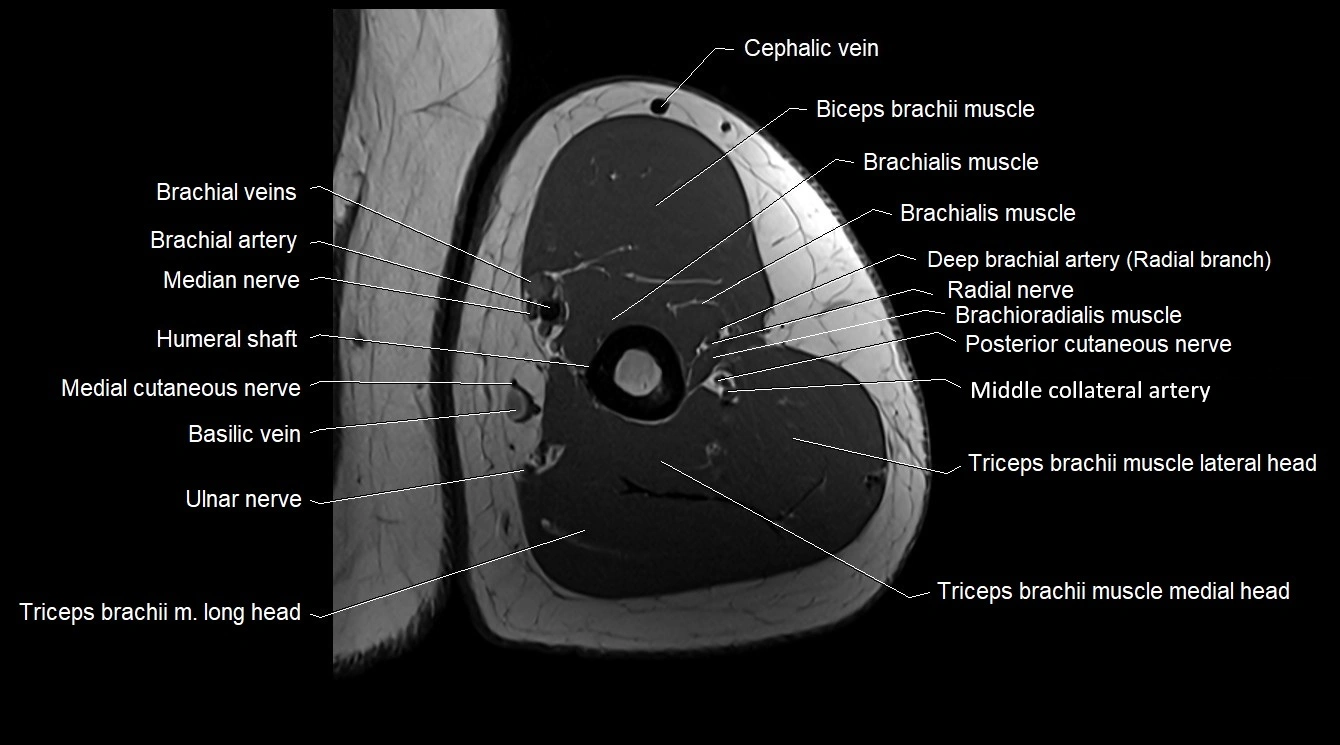

MRI image